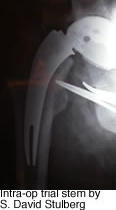

Evaluations of instrumentation, trial stems and final implants have been carried out successfully.